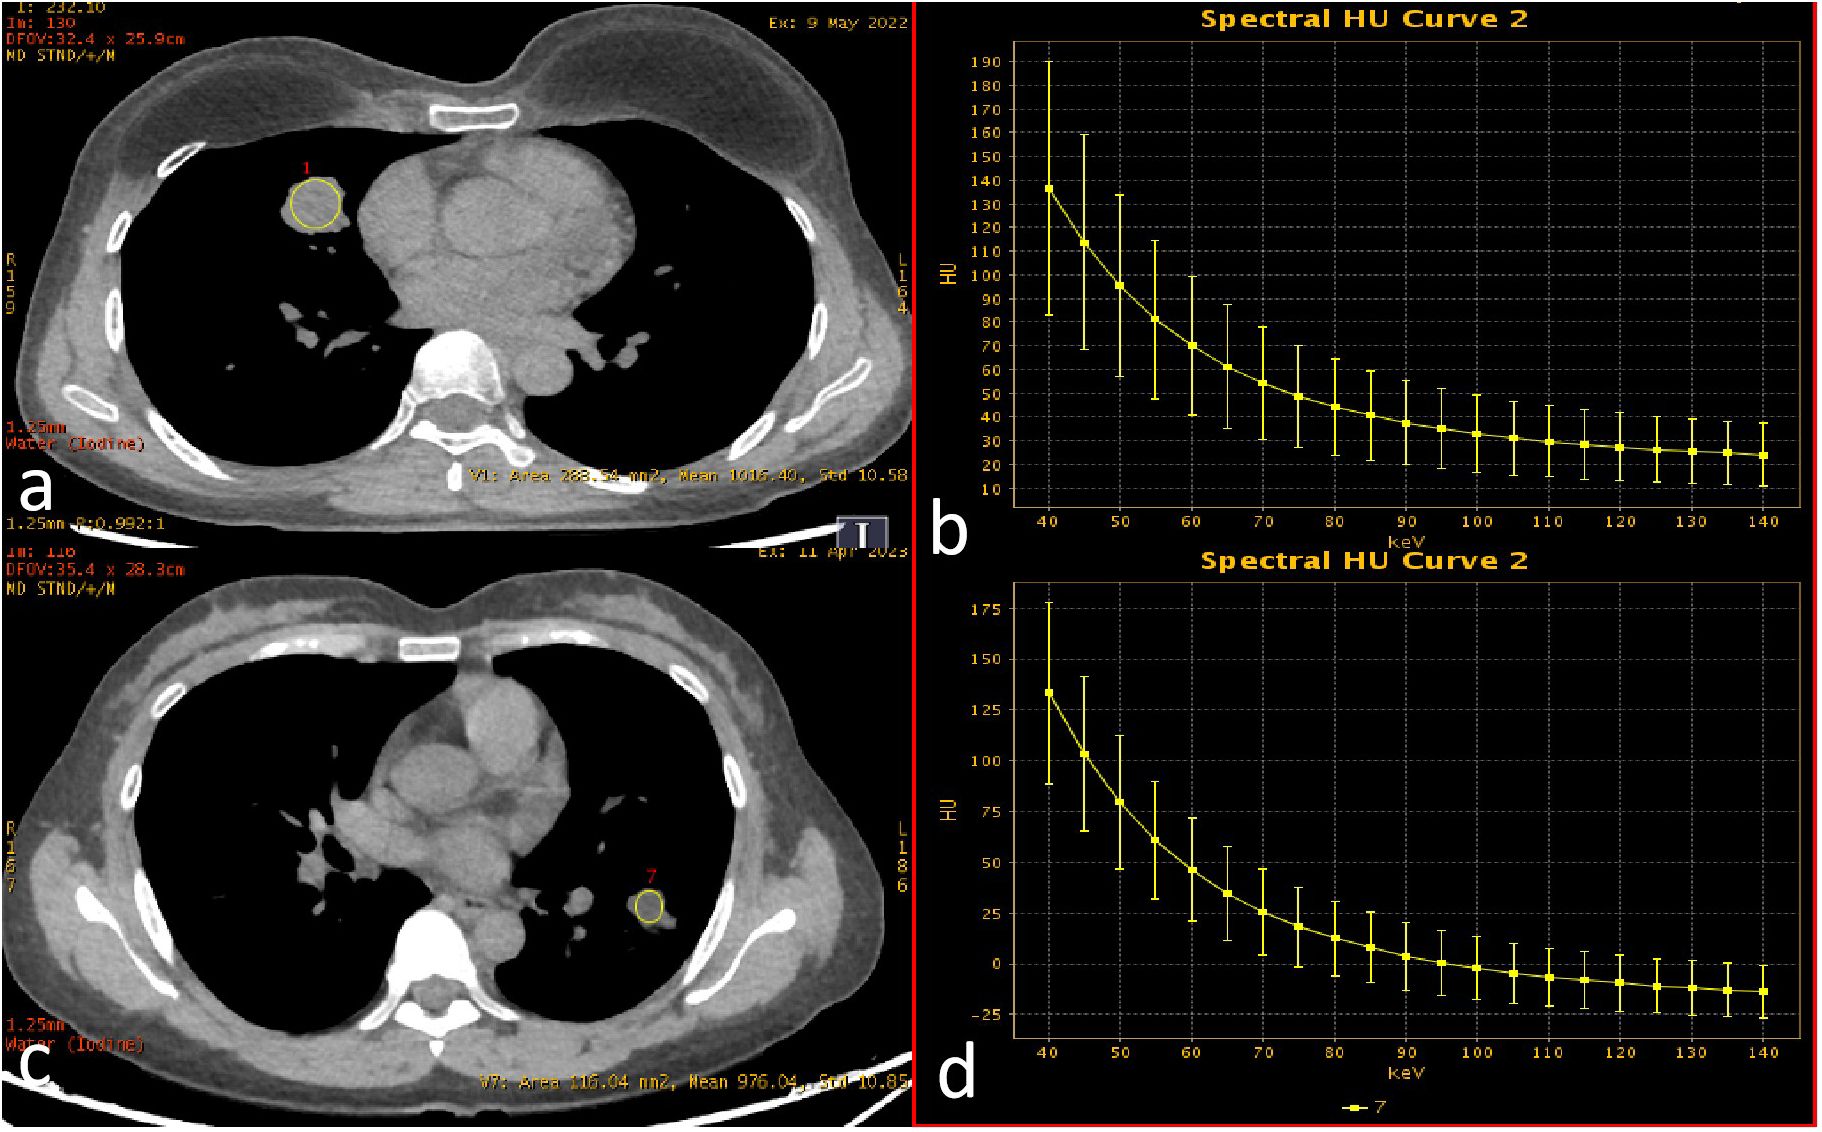

Non-contrast CT images (1.25 mm slice thickness, lung window: width 1200~1500 HU, level -600~-800 HU) were processed using an AI-powered pulmonary nodule analysis system (Infervision V4.0, Beijing, China). The system employs a pre-trained convolutional neural network to extract quantitative features from lesions in routine pulmonary CT examinations, with prior training and validation performed on CT datasets encompassing diverse acquisition parameters. The system automatically segmented tumors and generated 18 quantitative biomarkers: Three-dimensional (3D) radiomic features(including long-axis diameter, short-axis diameter, surface area, 3D long-axis diameter, maximum cross-sectional area, volume), CT attenuation histogram features(including solid component percentage, mean CT value, median CT value, CT value standard deviation, maximum CT values, minimum CT values, kurtosis, skewness, energy, and entropy)and morphological characteristics(including compactness, sphericity). Three-dimensional (3D) radiomic features enable a more comprehensive quantification of tumor burden. CT attenuation histogram features reflect intratumoral density variations, potentially indicative of pathological alterations such as necrosis, hemorrhage, or cellular proliferation. While morphological characteristics capture shape complexity, which may correlate with aggressive growth patterns and spatial heterogeneity. The AI-based pulmonary nodule diagnostic system leverages a deep learning algorithm to perform automatic segmentation of nodule boundaries and identification of typical radiological signs. For component analysis, the algorithm applies a threshold of -145 HU to differentiate solid from non-solid components within the nodule. It then calculates the number of voxels corresponding to each CT attenuation value, storing this data in a histogram. Subsequently, volumetric and other three-dimensional metrics are computed based on voxel counting (Figure 2) (1719). Two board-certified radiologists independently validated AI-derived tumor segmentation accuracy through consensus review, ensuring spatial correspondence between imaging findings and postoperative histopathology.

CT scan of a thoracic cross-section shows lungs with a highlighted region in the right lung indicating an area of interest. Below is a graph depicting voxel distribution with solid and non-solid components. Key statistics include max CT value of 522, min CT value of -522, and a mean of -84. Metrics like compactness, sphericity, and kurtosis are listed, along with a solid component percentage of 66.99%.

Figure 2. AI-derived CT histogram parameters. The solid component percentage was defined as the total number of voxels with CT attenuation ≥ -145 Hounsfield Units (representing the solid component) divided by the total number of voxels encompassing the entire tumor.